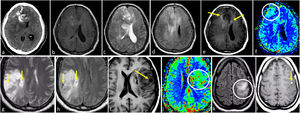

Glioblastoma molecularLas manifestaciones radiológicas típicas del glioblastoma pueden no ser aplicables en aquellos casos que no están definidos histológicamente sino solo desde el punto de vista molecular (TERT, EGFR, 7+/10-), para los que las imágenes siguen siendo relativamente desconocidas. Pueden presentarse como lesiones infiltrantes mal definidas en las secuencias T2w y FLAIR, con realce mínimo o nulo, sin necrosis y sin hallazgos patológicos en DWI y DSC-PWI. De hecho, pueden observarse con un aspecto histológico clásico de grado 2-3. Sin embargo, según algunos estudios, hay una tendencia a la multifocalidad y multicentricidad, así como un patrón giriforme de infiltración cortical en los tumores con mutaciones en EGFR o TERT54–56. Desde un punto de vista práctico, la presencia de un patrón de gliomatosis cerebral (con posibleas areas de infiltración cortical giriforme) en un adulto mayor de 55 años puede hacer sospechar la presencia de un glioblastoma molecular, en particular con mutación en TERT54–56 (fig. 4). No se han encontrado descripciones cualitativas de imágenes para los casos con ganancia del cromosoma 7 y pérdida del 10.

Posible presentación de glioblastoma IDH-wildtype con alteración molecular de TERT o EGFR. Dos pacientes, uno de 80 años (a-c) y otro de 55 años (d-f). En secuencias FLAIR axiales (a-b y d-e), hiperintensidades infiltrantes difusas y extensas que recuerdan un patrón de gliomatosis cerebral en glioblastomas con mutación del promotor TERT. Las imágenes T1w poscontraste (c y f) no muestran realce ni signos de necrosis.

EGFR: receptor del factor de crecimiento epidérmico; IDH: gen isocitrato deshidrogenasa;

TERT: transcriptasa inversa de la telomerasa.

Según los supuestos de publicaciones anteriores a la 5.a edición, estos tumores podrían presentarse en las imágenes como lesiones infiltrantes mal definidas, con realce mínimo o nulo, sin necrosis y sin hallazgos patológicos en DWI o DSC-PWI. Pueden exhibir márgenes más mal definidos y posible propensión a una localización temporal, así como ausencia de mismatch T2/FLAIR en comparación con los mismos grados, pero IDH-mutados57 (fig. 5). Desde la perspectiva del abordaje radiológico, los autores recomiendan tener en cuenta el papel de la radiolgía en los siguientes aspectos: 1) guiar las biopsias para localizar las regiones de los tumores con mayor grado y 2) analizar atentamente las imágenes para identificar marcadores de grado histológico 4 que puedan no haber sido captados en la biopsia. Estas prácticas deberían minimizar los posibles sesgos de biopsia y la infraestimación del grado del tumor31.

Dos casos de ejemplo en los que los resultados de la biopsia podrían corresponder a un grado histológico 2-3 para un tumor que en realidad sería de grado 4. a-c) Paciente de 57 años. FLAIR axial (a), T1w poscontraste (b) y mapas de color de CBV derivados de DSC-PWI (c). Extensa lesión infiltrante temporal medial izquierda hiperintensa en FLAIR (a), sin realce ni necrosis (b), y un sutil foco nodular de CBV claramente elevado (círculo en c). Es decir, con una biopsia que no captara los focos de CBV elevado se correría el riesgo de subestimar el grado este tumor astrocítico IDH-wildtype como grado 2-3 (NEC) en el estudio anatomopatológico. d-f) Paciente de 58 años. FLAIR axial (d), T1w poscontraste (e) y mapas de color de CBV derivados de DSC-PWI (f). Extensa lesión infiltrante temporal medial izquierda hiperintensa en FLAIR en (d), con un área más focal de realce prominente y necrosis (flecha en e), así como CBV elevado (círculo en f). Es decir, con una biopsia que no captara la necrosis o el componente de CBV elevado se correría el riesgo de subestimar el grado este tumor astrocítico IDH-wildtype como grado 2-3 (NEC) en el estudio anatomopatológico. Se trató a ambos pacientes como glioblastomas IDH-wildtype según la decisión consensuada de un comité de neurooncología.

CBV: volumen sanguíneo cerebral; DSC-PWI: imagen de perfusión dinámica; IDH: gen isocitrato deshidrogenasa; NEC: not elsewhere classified.